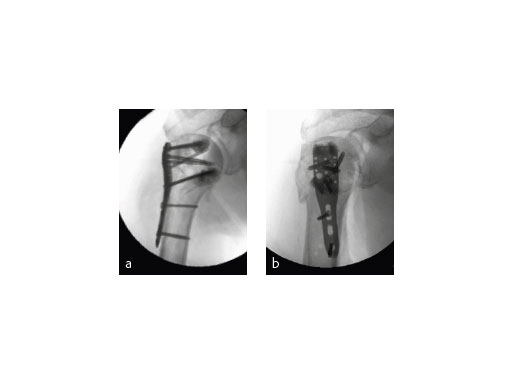

The fracture was treated with PHILOS augmentation and healed in anatomical position (Fig 9).

(Case 2 provided by Franz Kralinger, Innsbruck, Austria)